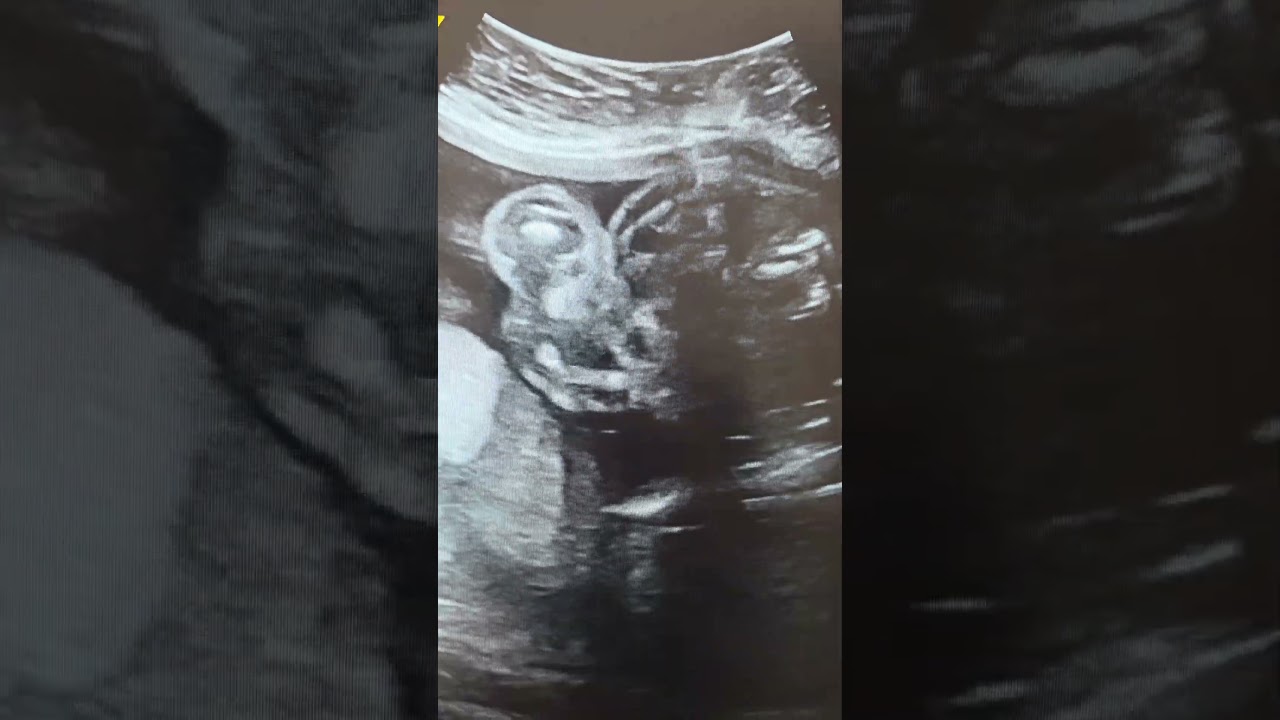

Ultrasound Report (20 Weeks Gestation):

Fetal anatomy survey demonstrates echogenic bowel. The bowel appears as bright as, or brighter than, the adjacent bone. This finding is considered a soft marker for certain chromosomal abnormalities and other conditions on second-trimester screening.